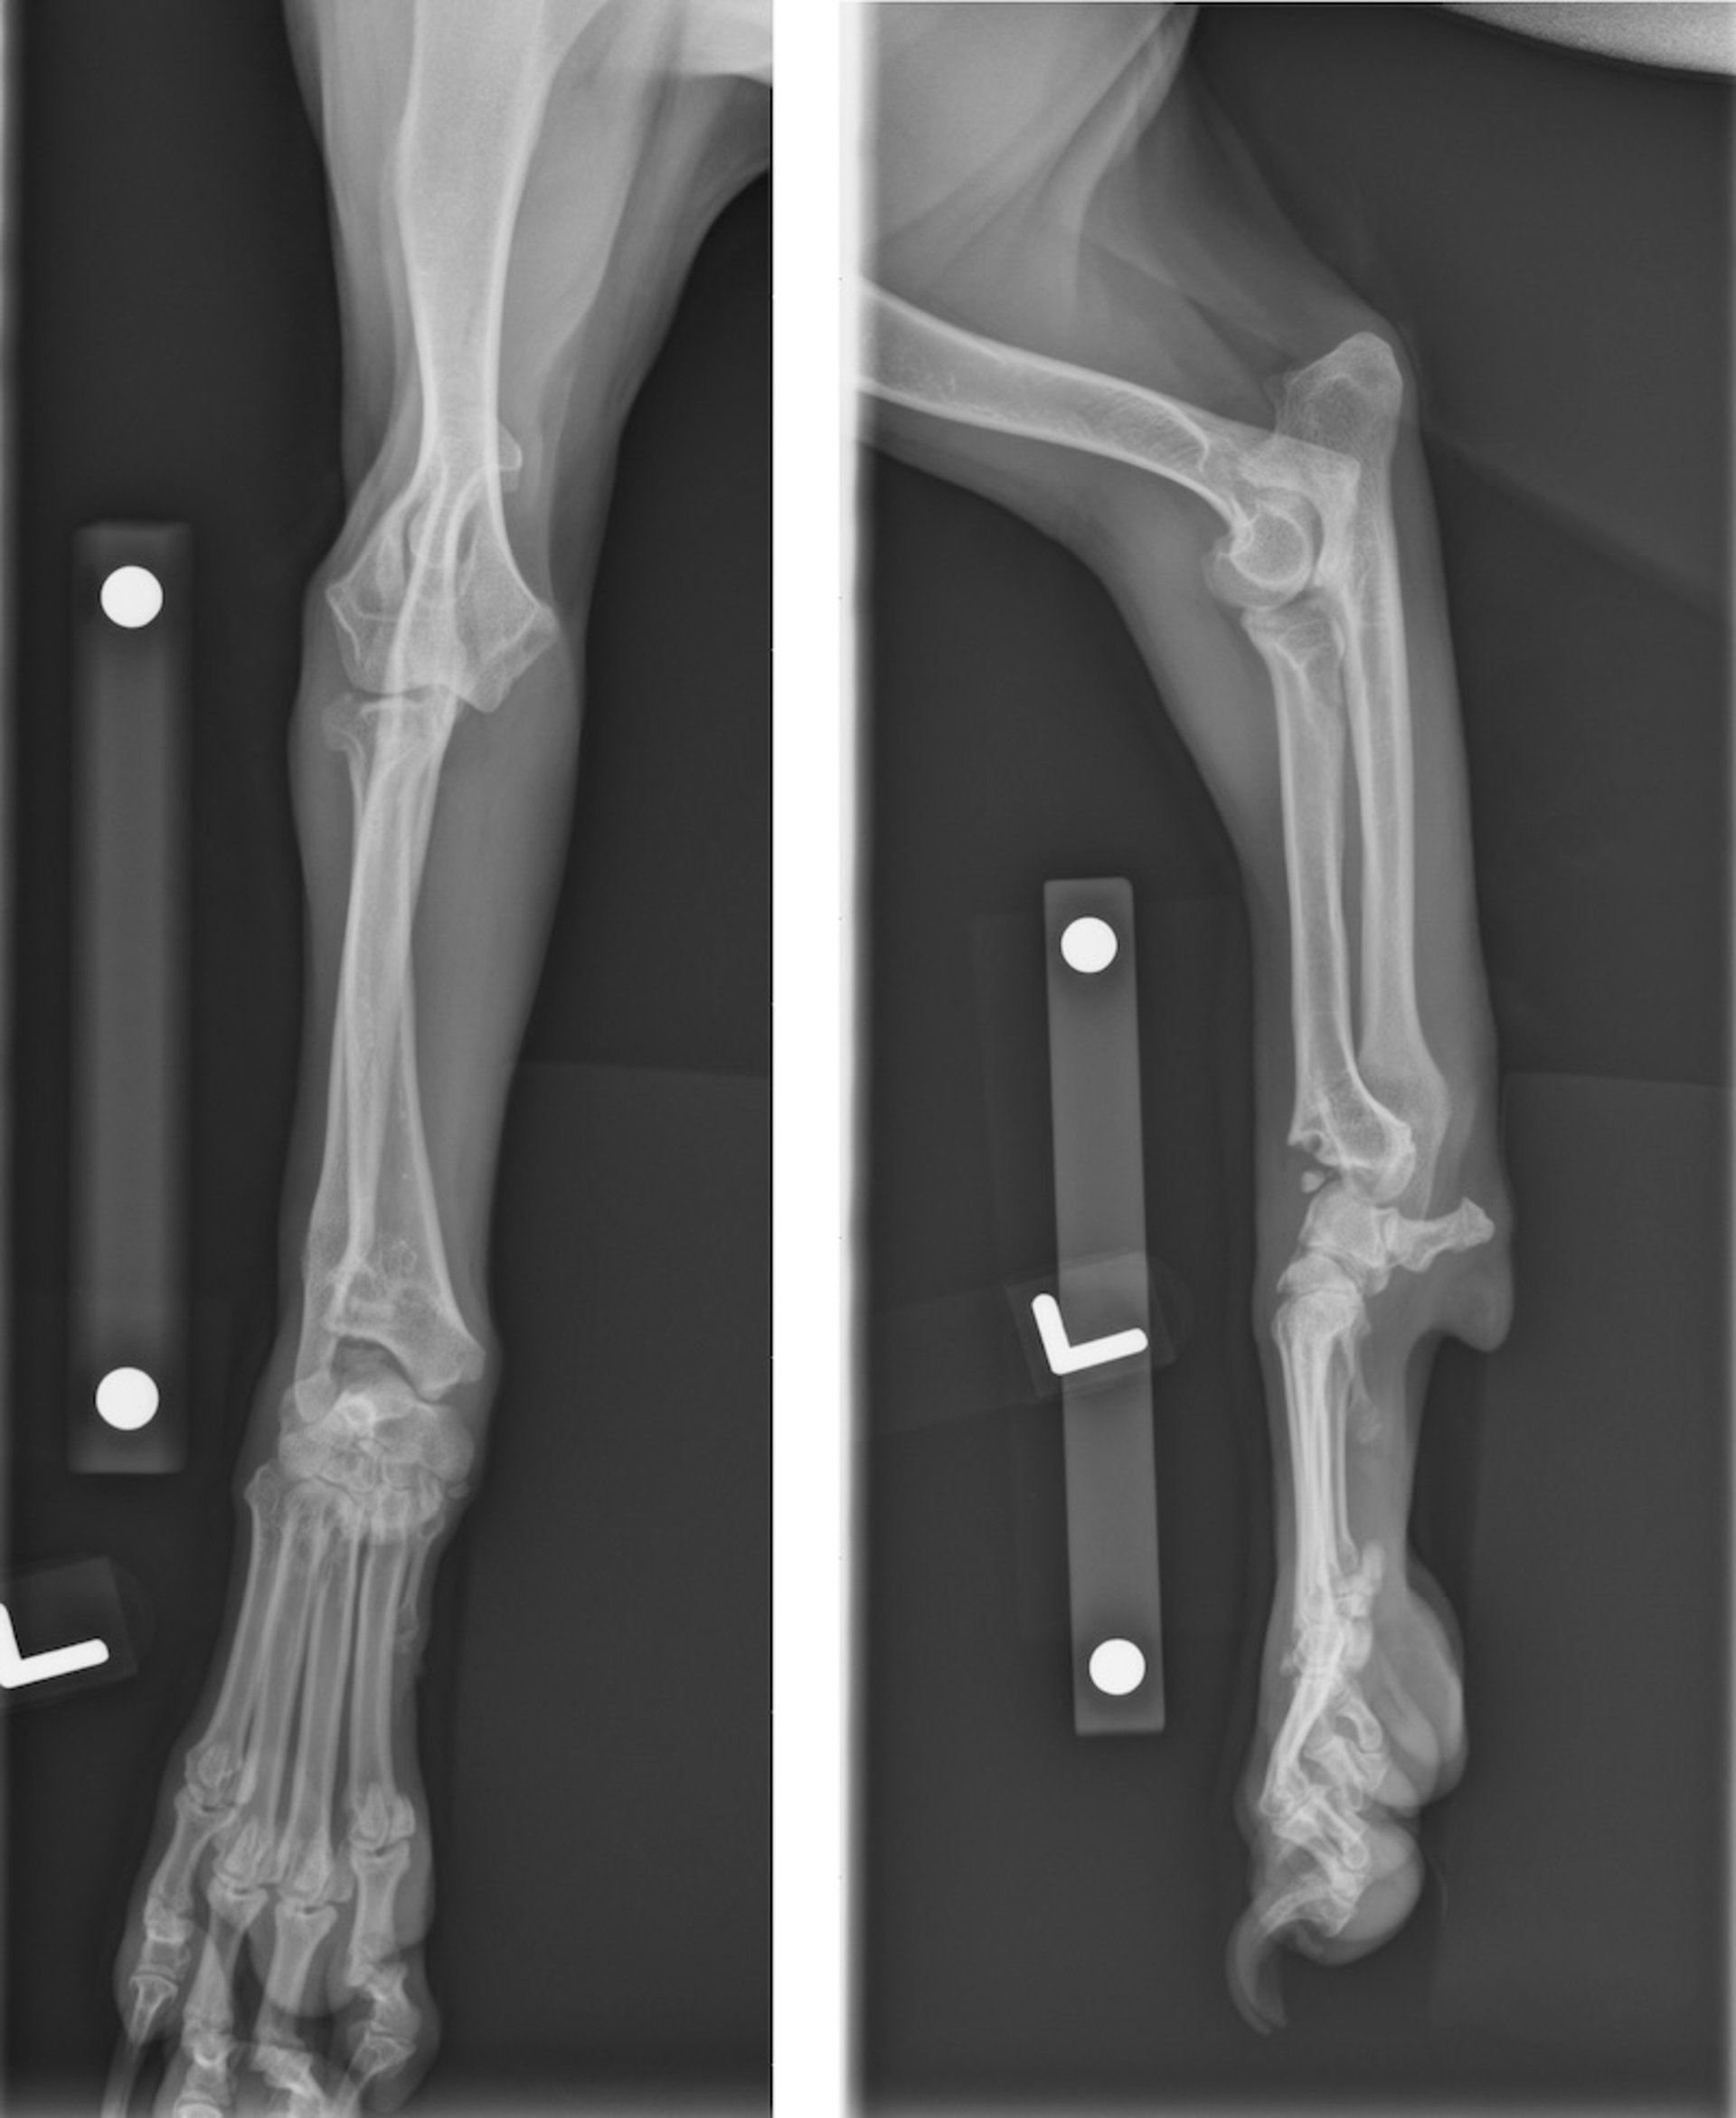

Angular limb deformity, radiographs, dog

Radiographs showing premature closure of distal ulnar and radial physis in an 8-month-old mixed-breed dog. Short radius and ulna, carpal joint subluxation, and incongruity of radioulnar, humeroulnar, and radioulnar joints are evident.

Courtesy of Dr. Po-Yen Chou.